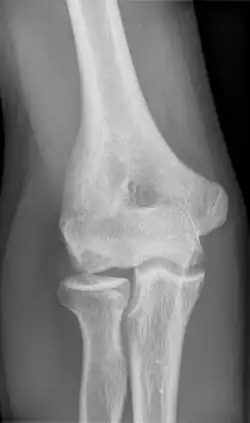

Panner disease is an osteochondrosis of the capitellum of the elbow.[1] Panner disease is primarily seen in boys between the ages of five and ten years old.[2] Panner disease is often caused by excessive throwing due to valgus stress. The disease causes pain and stiffness in the affected elbow and may limit extension; the affected elbow is usually on the dominant arm the child uses.[3] The disease may be associated with pitching and athletic activity. On radiographs, the capitellum may appear irregular with areas of radiolucency. Treatment is symptomatic, with a good prognosis. Treatment is minimal and includes restricting athletic activity to allow for the elbow to heal and for pain to be relieved.[4] The disease is named after the Danish radiologist Hans Jessen Panner (1871–1930).

To confirm the diagnosis, an x-ray or MRI scan will be done. The radiograph will enable the doctor to visualize irregularities and see the shape of the capitellum and also visualize the growth plate. In Panner Disease, the capitellum may appear flat and the bone growth plate will look irregular and fragmented. The areas where bone breakdown has occurred can also be visualized on the radiograph.[2] When the patient undergoes an MRI scan any irregularities of the capitellum will be able to be visualized, and the bone will be able to be visualized in more detail to determine the extent of swelling, if any. In the MRI results for Panner disease, there will be a decreased signal intensity of the capitellum on a T1 series and increased signal intensity on a T2 series.[2][5]

Although the exact cause of Panner Disease is unknown, in recent research, it has been concluded that it may be associated with frequent throwing or other athletic activity.[4] In the same article that talks about varying osteochondrosis diseases, it is pointed out that Panner Disease always involves alteration of the capitellum, which can be visualized by radiography. In another research article, the research team aimed to summarize the best available evidence for diagnosis and treatment for Panner Disease. In the article it was found that the most common symptoms that patients with Panner Disease present with are elbow stiffness and swelling, limited range of motion, and limited elbow extension.[2] In alignment with the previously mentioned article, the team of researchers also concluded that Panner Disease involves irregularity of the capitellum, specifically that it appears flattened. Panner Disease often gets misdiagnosed as osteochondritis dissecans (OCD), and in this article they distinguish the difference between the two diseases are age difference and radiographic findings.[2] In alignment with the two previously discussed articles, another article that reports on three case studies of Panner Disease, states that the primary treatment that is used for Panner Disease is rest and restriction from all physical and athletic activity that involves the use of the upper extremities; the activity is suggested to be ceased until the symptoms are relieved.[5]